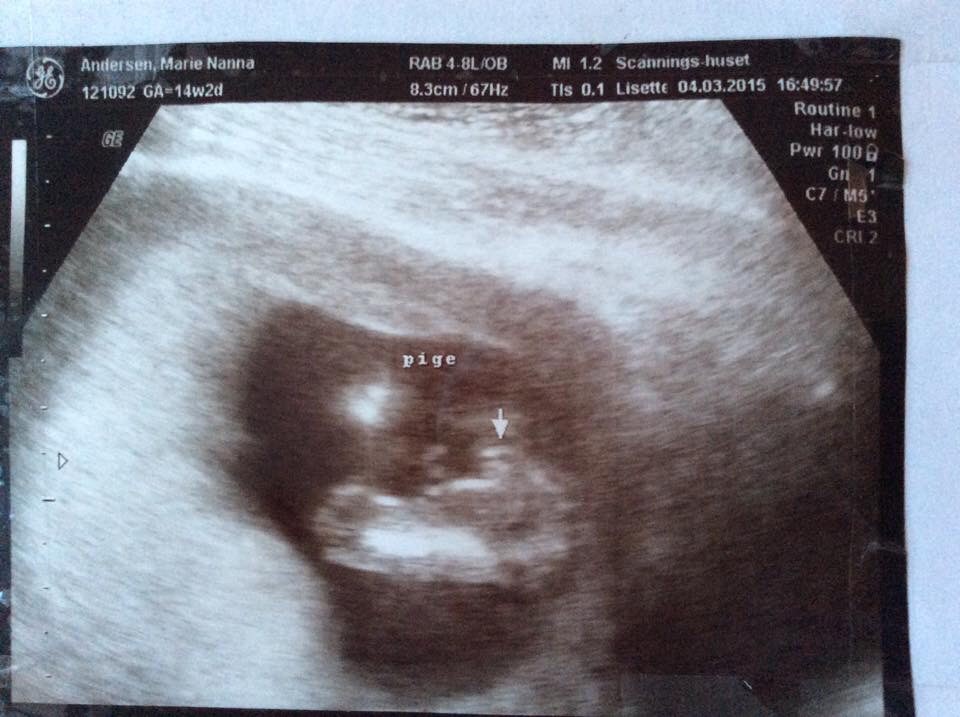

Min mand og jeg var til 3d scanning i uge 27, hvor vi fik lavet en video. Vi havde sagt vi ikke ville kende kønnet, så vi lukkede øjnene i starten af scanningen, mens lårbenet blev målt. Jordemoderen sagde dog at man tydeligt kunne se kønnet.

Nu kort inden fødslen blev vi lidt nysgerrige og fandt videoen frem. Vi er dog overhovedet ikke vant til at kigge på sådan nogle billeder, så vi synes det er svært at se, men vi har et bud

Er der nogen er jer der tør gætte?

Billederne er taget hvor baby har numsen i vejret, har prøvet at illustrere det på billederne